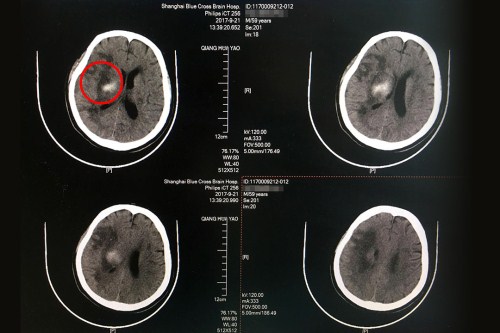

术前CT:右侧基底节区大量出血,血肿破入脑室系统,右侧高颅压。

术后CT:右侧额颞枕叶梗塞伴右侧基底节区出血吸收中,皮层血供再通,较前好转